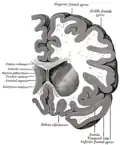

Transverse cut of brain (horizontal section), basal ganglia is blue | |

Along with the putamen, the caudate forms the dorsal striatum, which is considered a single functional structure; anatomically, it is separated by a large white-matter tract, the internal capsule, so it is sometimes also described as two structures—the medial dorsal striatum (the caudate) and the lateral dorsal striatum (the putamen). In this vein, the two are functionally distinct not because of structural differences, but merely because of the topographical distribution of function.

The caudate nuclei are near the center of the brain, sitting astride the thalamus. There is a caudate nucleus in each hemisphere of the brain. Each nucleus is C-shaped, with a wider "head" (caput in Latin) at the front, tapering to a "body" (corpus) and a "tail" (cauda). Sometimes a part of the caudate nucleus is called the "knee" (genu).[6] The caudate head receives its blood supply from the lenticulostriate artery; the tail of the caudate receives its blood supply from the anterior choroidal artery.[7]

The head and body of the caudate nucleus form part of the floor of the anterior horn of the lateral ventricle. The body travels briefly towards the back of the head; the tail then curves back toward the anterior, forming the roof of the inferior horn of the lateral ventricle. This means that a coronal section (on a plane parallel to the face) that cuts through the tail will also cross the body and head of the caudate nucleus.